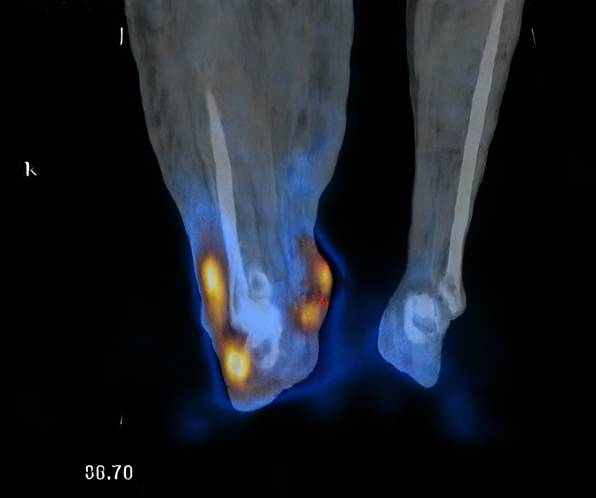

Lymphoscintigraphy findings

Seven patients underwent lymphoscintigraphy at 12 months. All demonstrated findings suggestive of functional improvement, including increased tracer uptake in the transferred omental flap (Figure 5), clearer visualisation of lymphatic trunks, reduced dermal backflow, and fewer collateral channels (Figure 6). Comparative analysis was not feasible in five patients due to flap failure (n = 1), loss to follow-up (n = 1), or incompatible preoperative imaging protocols (n = 3).

Figure 5

Radiotracer uptake detected in the omental flap (indicated by red dots).

These findings are consistent with previous reports by Ciudad et al.[12] and Nguyen et al. [18, 22], who demonstrated clinical and functional improvement following laparoscopic omental VLNT. Our results are further corroborated by recent extensive clinical experiences reported by Pozzi et al., which reaffirmed that gastroepiploic VLNT is a highly effective and safe procedure for extremity lymphedema, offering significant improvements in limb circumference and tissue tonicity with minimal donor-site morbidity [26]. Notably, our lymphoscintigraphy suggested not only improved drainage but also radiotracer uptake within the transferred flap, supporting the concept of neo-lymph node formation through lymphangiogenesis and functional integration into the host lymphatic network. This aligns with prior experimental studies showing that transplanted lymph nodes secrete VEGF-C and VEGF-D, which stimulate VEGFR-3-mediated lymphangiogenesis and promote the regeneration of lymphatic sinuses and high endothelial venules (HEVs) [12, 18, 22].

The observed greater reduction in distal limb circumference further supports the biological mechanism: placing the omental flap at the ankle optimises gravitational drainage and provides a local microenvironment for lymphangiogenesis. The improved uptake and reduced dermal backflow on lymphoscintigraphy are consistent with the establishment of new lymphatic pathways and the functional maturation of neo-lymph nodes.